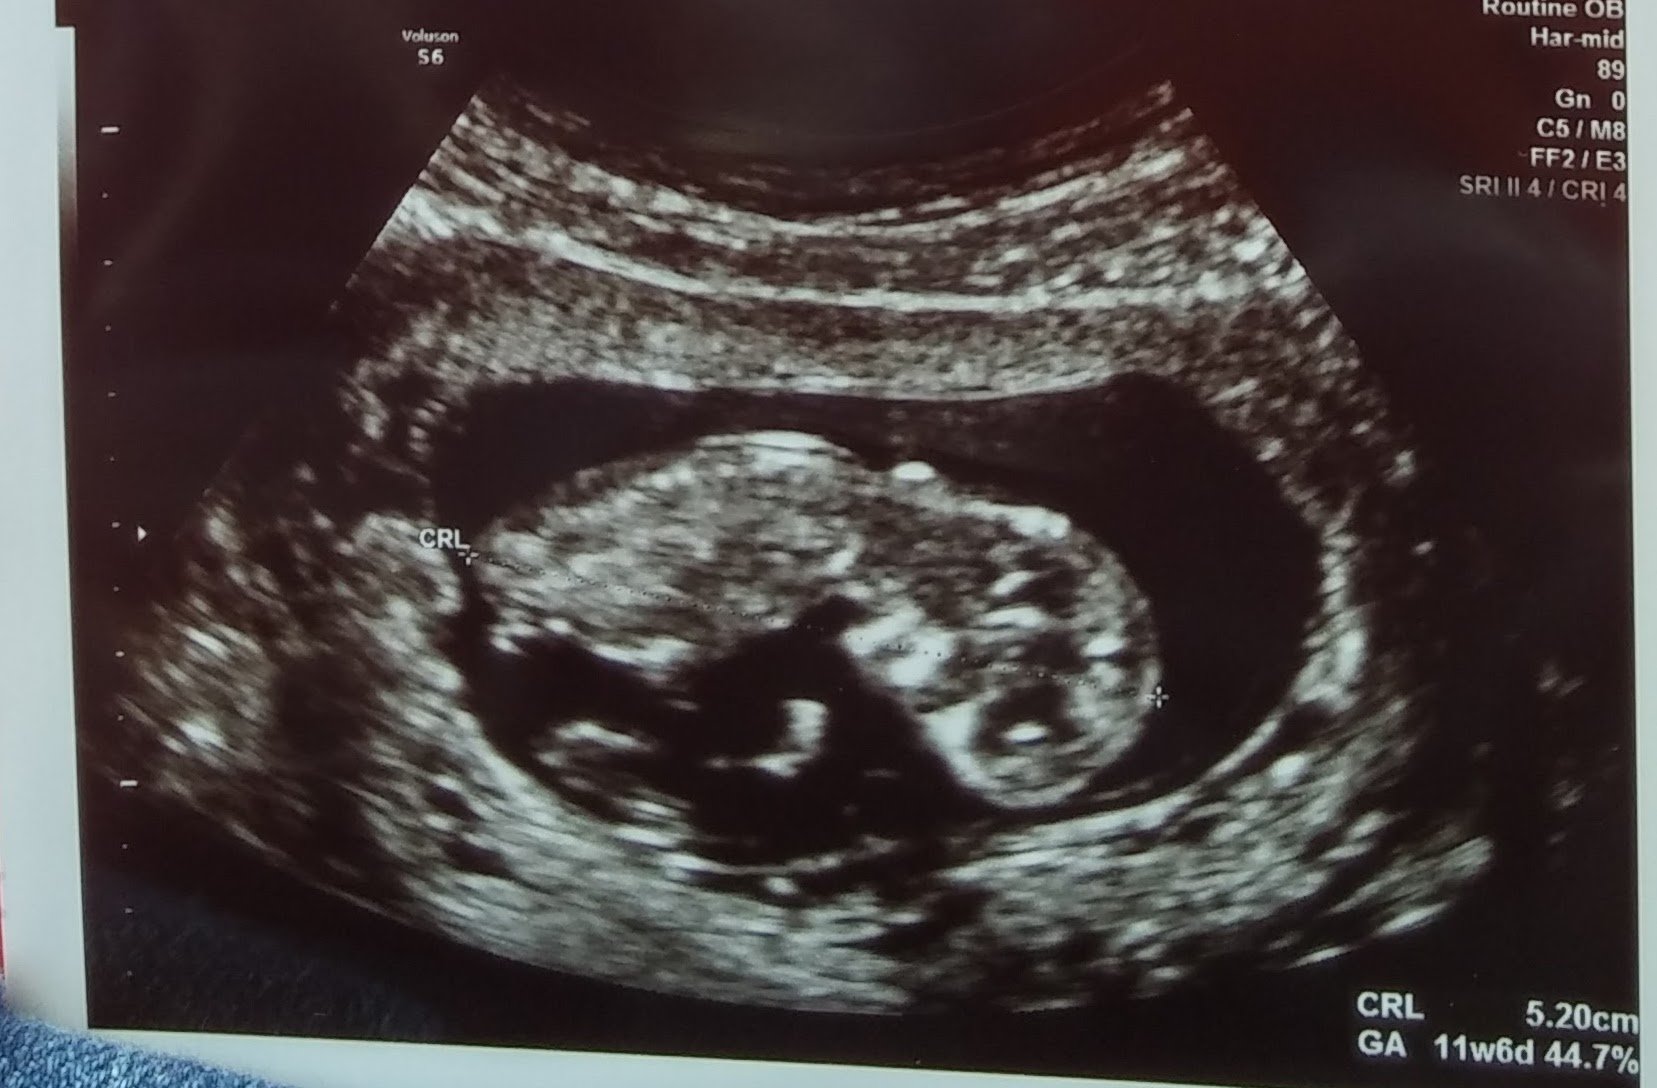

This is our little one looking more and more like a baby every day. Baby was facing the transducer and covering her face so we got some pics of her little hands and saw her cute face on the US! ETA: This was at 11w6d, baby measuring 12w3d.